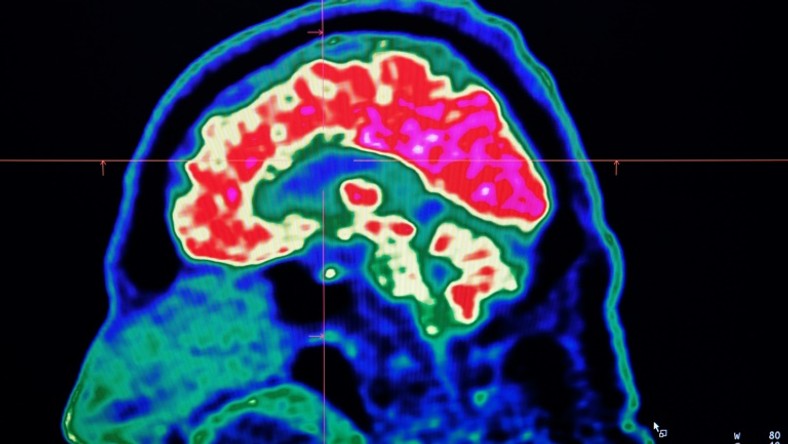

Yarimar Carrasquillo, the paper's senior author and a scientist for the National Center for Complementary and Integrative Health (NCCIH), told AFP the region responsible was the central amygdala, which according to her work appeared to play a dual role.

Studying mice, Carrasquillo and her colleagues found that the activity in neurons that express protein kinase C-delta amplified pain, while neurons that express somatostatin inhibited the chain of activity in the nerves required to communicate pain.